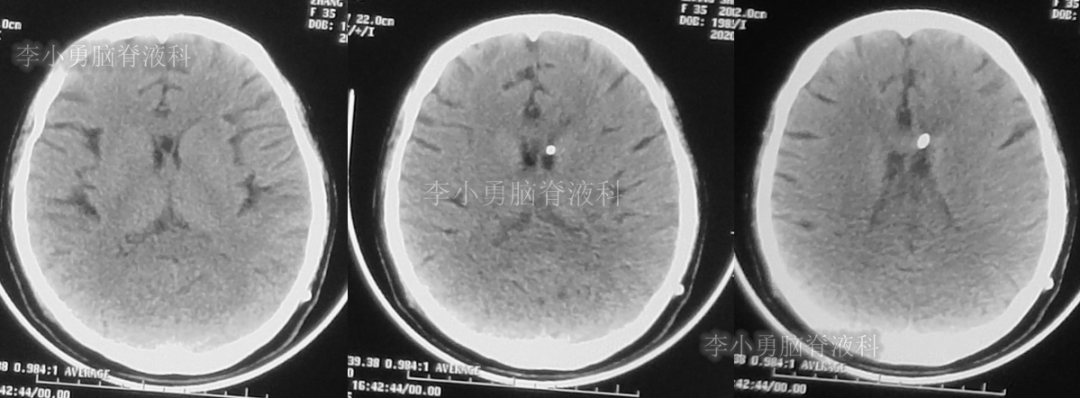

入院时(2020年2月21日)头颅CT(图-22)见脑室缩小,呈裂隙状。

图-22:2020年2月21日头颅CT